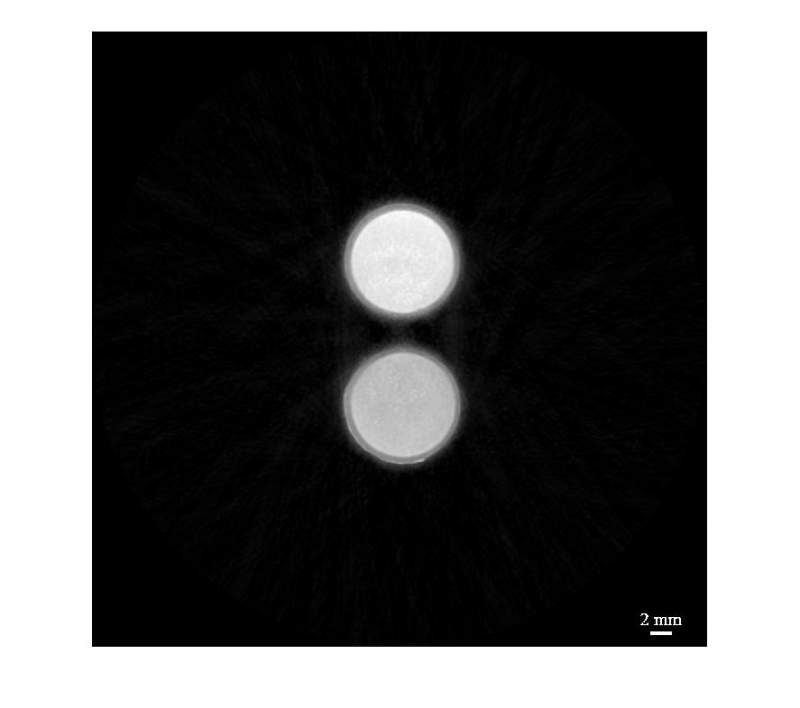

x射线能谱调制与CT切片数据处理之间的联系 已有1人参与